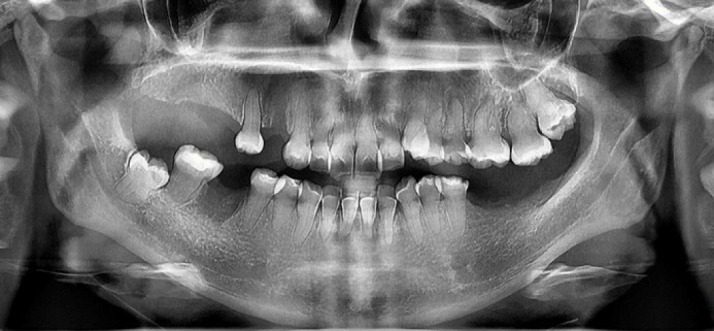

Pulp canal calcification (PCC) is common in patients with dentinogenesis imperfecta (DGI). We present endodontic management of multiple anterior and posterior teeth with PCCs in a patient with DGI type II using guided endodontics. A 26-year-old female patient was diagnosed with DGI type II. Clinical examination revealed palatal cusp fracture in tooth #13, microcracks in tooth #14, and a sinus tract in the maxillary right buccal vestibule related to tooth #13. Periapical radiographs revealed PCCs in all teeth, and periapical radiolucencies in several teeth. Due to difficult negotiation of canal orifices, guided endodontic approach was planned. Cone-beam computed tomography (CBCT) was requested and obtained. Intraoral scanning was performed, and CBCT and intraoral scanning data were superimposed. A template was designed and 3D printed. The root canal orifices were successfully negotiated and endodontic treatments were successfully accomplished. At the 1-year follow-up, the endodontically treated teeth were asymptomatic, and periapical lesions were healing.